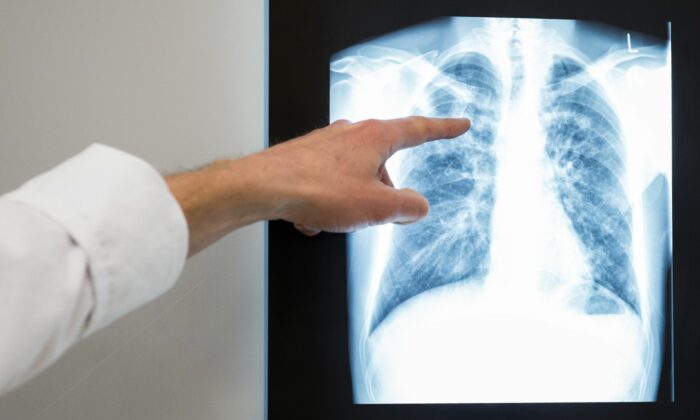

Tuberkulose ist eine der häufigsten Infektionskrankheiten. Die Bakterien werden von Kranken durch Tröpfcheninfektion, also zum Beispiel durch Husten, übertragen. Die Krankheit, die vor allem die Lunge betrifft, bricht teils erst Jahre nach der Infektion aus. Tuberkulose ist vermeidbar und behandelbar. Ohne Behandlung stirbt etwa die Hälfte der Patienten.